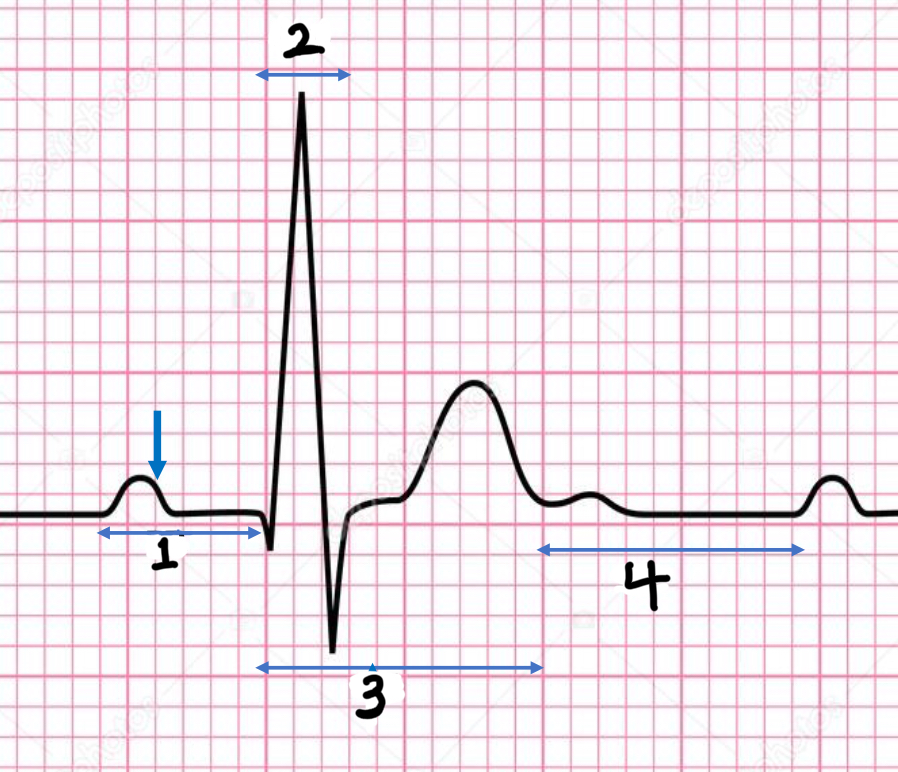

P wave

atrial depolarization

Precedes atrial contraction

QRS complex

ventricular depolarization

Precedes ventricular contraction

T wave

ventricular repolarization

PR interval

Name #1

QRS interval

Name #2

QT interval

Name #3

TP interval

Name #4

PR interval

time from beginning of the P wave to the beginning of the QRS complex

QRS interval

Time from beginning of the QRS complex to the end of the QRS complex

QT interval

Time from beginning of QRS complex to the end of the T wave

TP interval

Time from end of T wave to the beginning of P wave